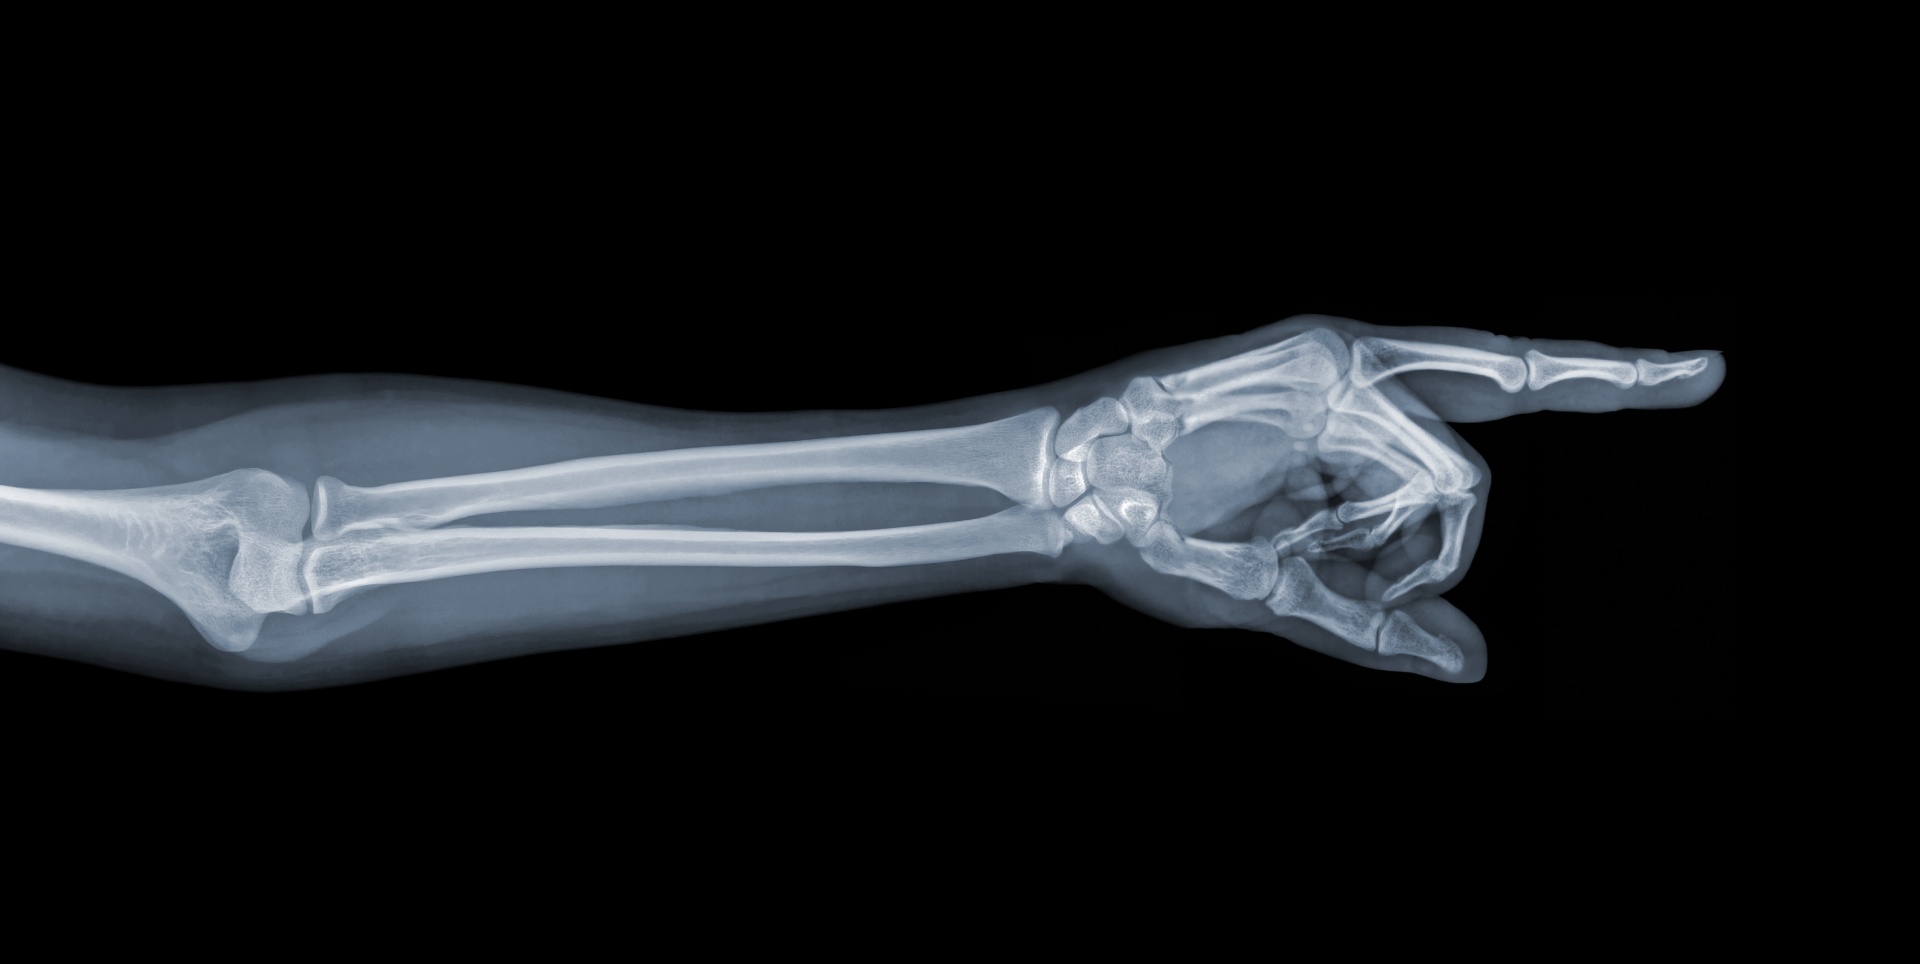

First described in 1814 by Abraham Colles, a Colles’ fracture is a break in the distal radius, one of the two forearm bones. It is considered an extra-articular fracture, meaning it does not directly involve the wrist joint, but it causes a characteristic displacement of the bone fragment.

The fractured segment is tilted and displaced toward the back of the hand and toward the thumb side.

This visible deformity is often called the “dinner fork deformity” due to its appearance.

The wrist is made up of several bones: the radius, ulna, and eight carpal bones. A Colles’ fracture is the most common type of distal radius fracture.